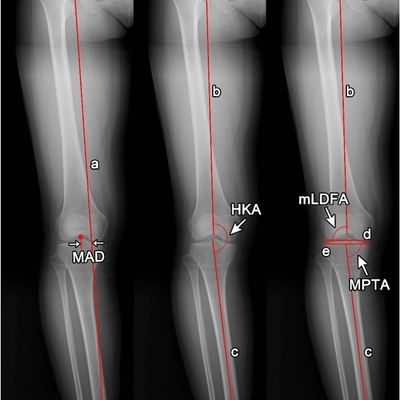

Click on an image below to view more info.